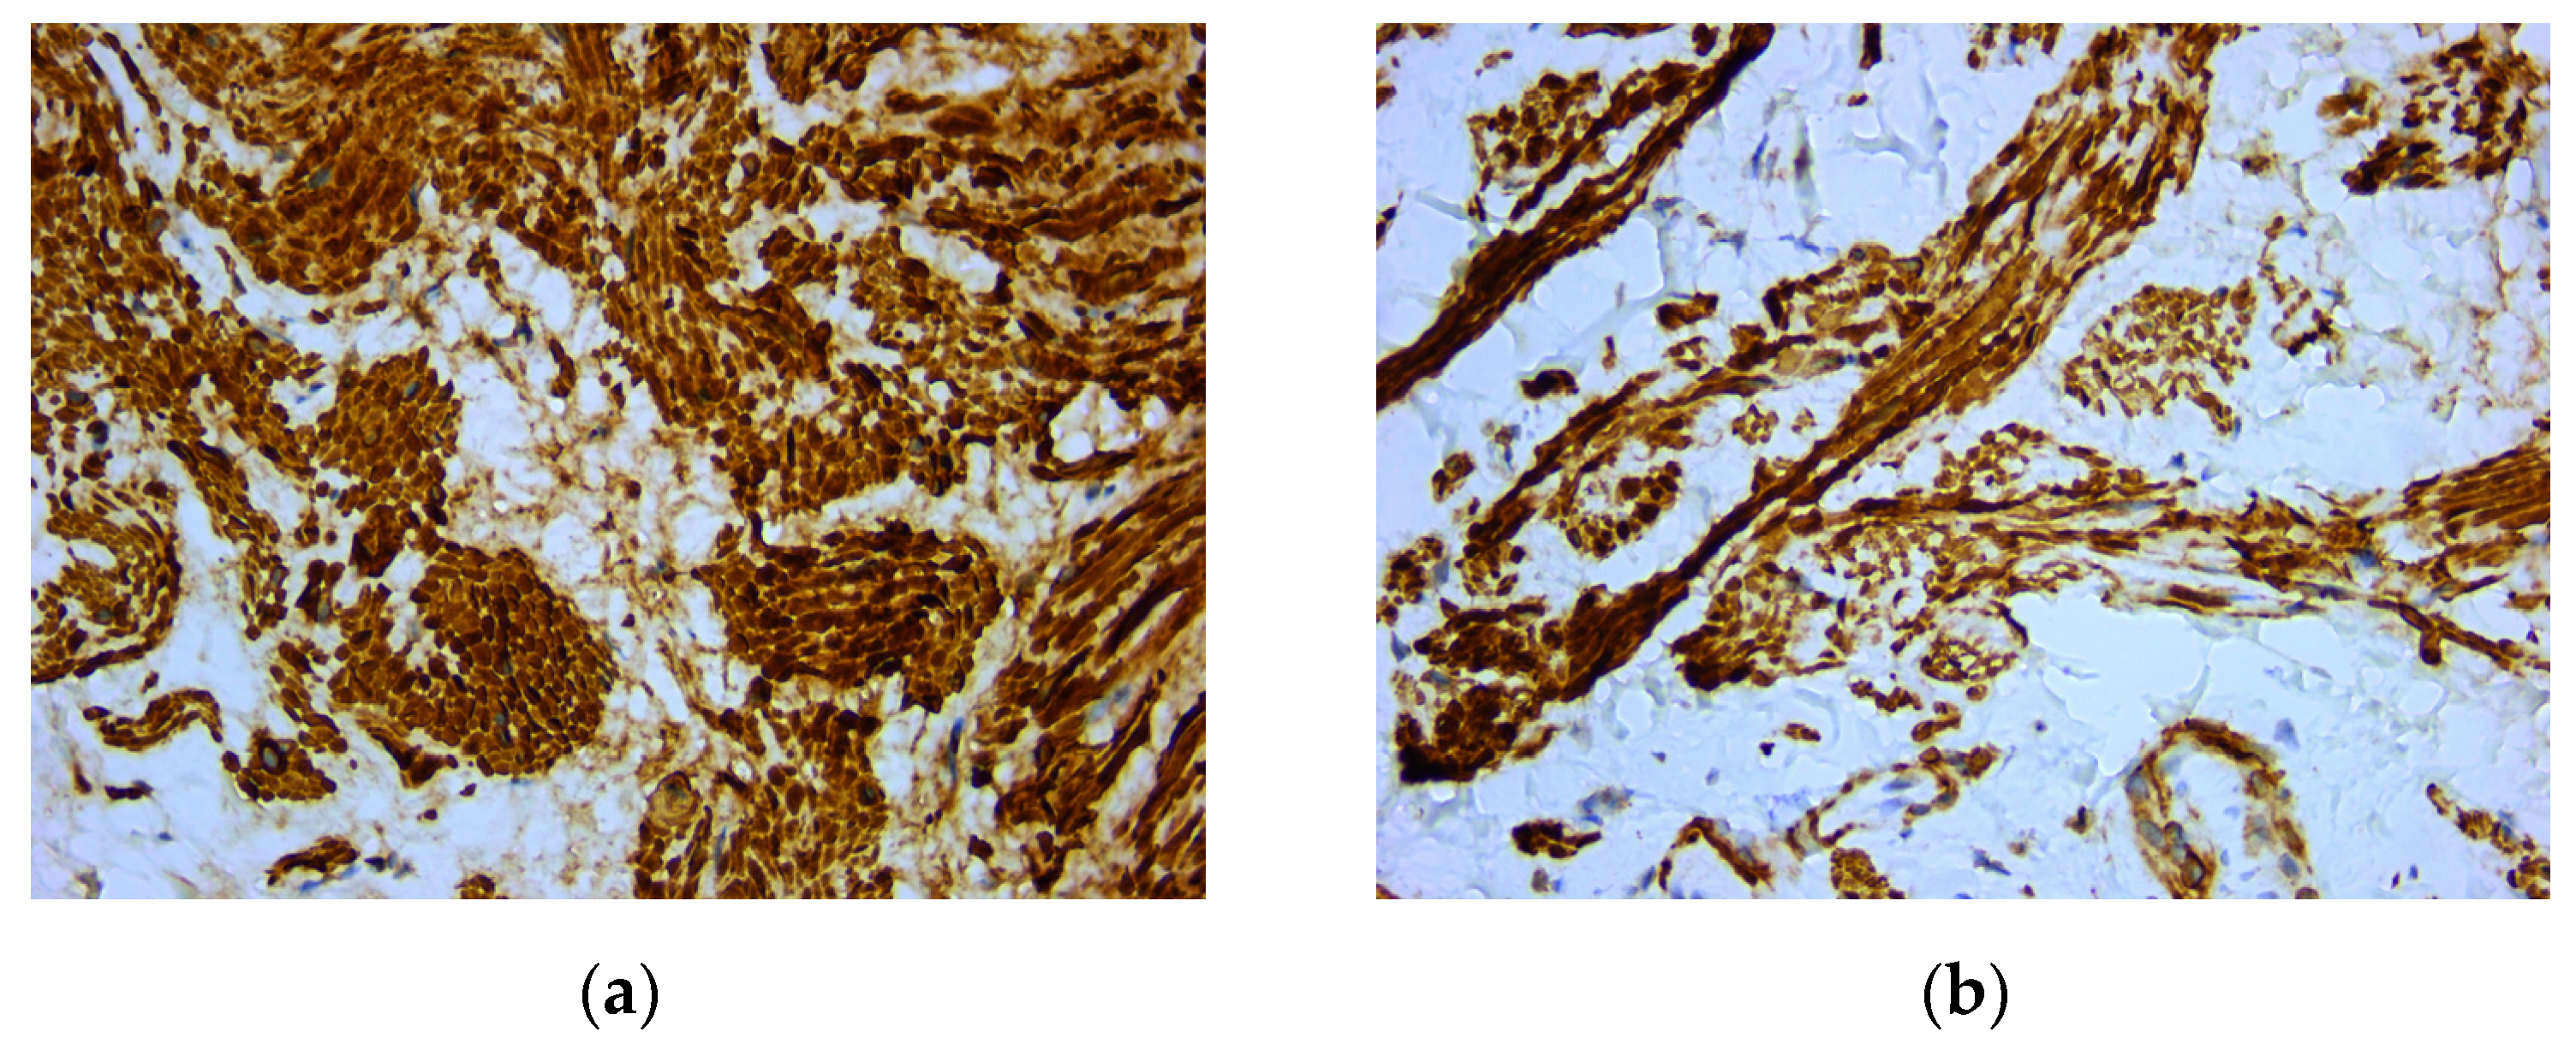

A cone beam computed tomography image (CBCT) did not reveal any changes of the subjacent bone structure in the anterior hard palate, suggesting the sole involvement of the soft tissue (Figure 2).

Figure 2. Cone beam computed tomography showed no underlying bone structure alteration.